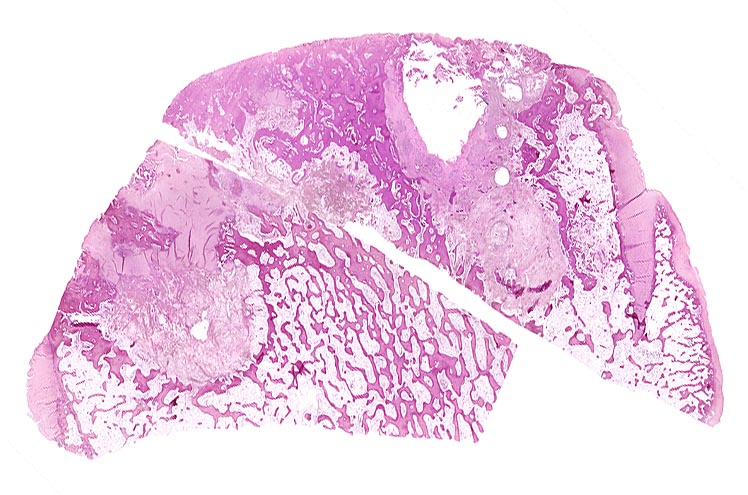

Der progrediente Knorpelverlust führt zum Freiliegen der knöchernen Deckplatte. Der subchondrale Knochen antwortet mit einer elfenbeinartigen Sklerose in Arealen vermehrter Belastung (=Eburnisation). Der traumatisierte subchondrale Knochen kann als Folge einer Knochennekrose pseudozystisch degenerieren (Geröllzystenbildung). Am Rand des Knochens, ausserhalb der Belastungszonen bilden sich irreguläre Knochenneubildungen (Randosteophytenbildung ev. mit Verdoppelung des Gelenkknorpels). Fragmentierungen dieser Osteophyten oder des Gelenkknorpels führen zu intraartikulären freien Körpern (=Gelenkmäuse) und einer Detritussynovialitis (> 1146) (> 1038) (> 539).

• Deformierte Gelenkfläche.

• Weitgehendes Fehlen des hyalinen Gelenkknorpels.

• Sekundäre Sklerose der freiliegenden Spongiosa mit Anbau von breiten Faser- und Lamellenknochensäumen an die alten Bälkchen.

• Leichte Osteoporose in der craniolateralen Entlastungszone.

• Herde von metaplastischem Faserknorpel in der Gelenkfläche.

• Randosteophyt, welcher über Resten des dort noch vorhandenen Gelenkknorpels entstanden ist (Verdoppelung des Knorpels).

• Nekrosebezirk in der Spongiosa (Geröllzyste) umgeben von einem Granulationsgewebssaum und Narbengewebe.